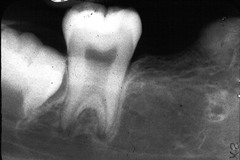

This type of cyst is also known as a periapical cyst; it occurs on non-vital teeth (infection); teeth with severe decay; pt. will complain of pain when biting down TX = extraction or Root Canal

Front

Radicular

Back